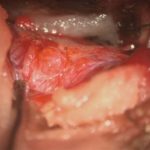

術中写真